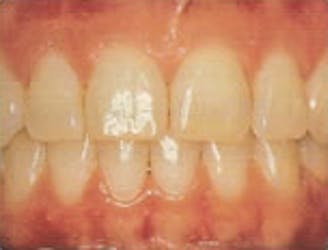

Healthy Gums

- Gums are a healthy pink color

- Gum line hugs teeth tightly

- No bleeding when brushing or flossing